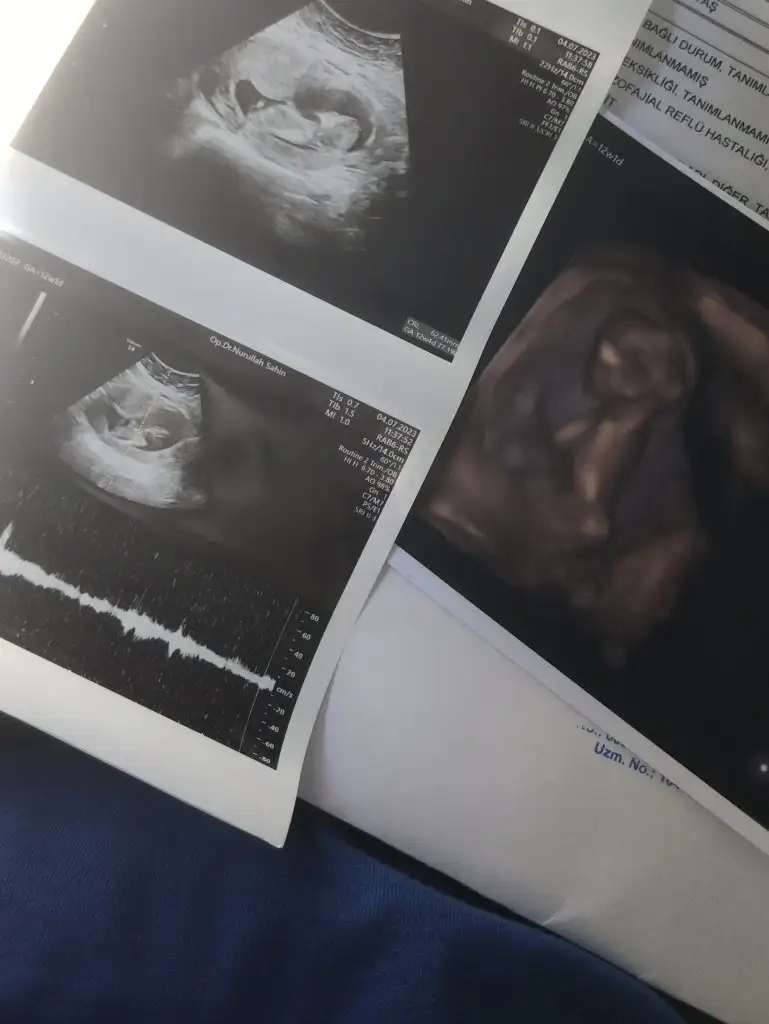

Kızlar selam. Dun kontrolumuz vardı ıkılı testımızı yaptırdık. Once ultrasonda 10-15 dakıka baktı doktorumuz. Baş popo 63 mm. Ense kalınlıgı 1.3 mm geldı. Burun kemıgı olusmus dedı. Mıde , bobrek olusmus dedı. Tek tek baktı. Kalbını dınledık. Zıplıyordu ıcerde 😍🧿 12+1 gelmesı gerekırken 12+4 geldı 🧿 cınsıyet ıcın yapısına gore bır yorum yaptı ama bacak arasını goremedık . Bır ay sonra netlesır dedı. Sızede atayım bı tahmınde bulunur musunuz 😍 ay bıde yan duruyodu dedıkı ıyıkı yuzustu degıl renklı ultrasonda oyle olsa korkarsın bu haftada dedı . Gozler falan yanda daha 🙈♥️🧿